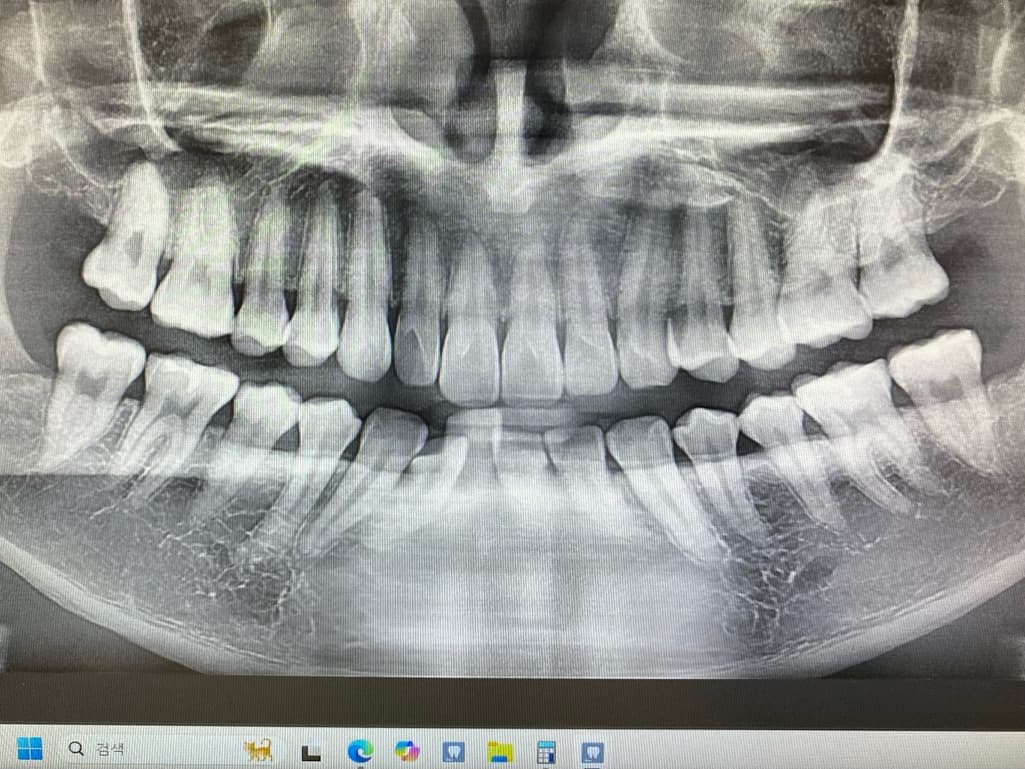

1번 치과는 왼쪽 위 4번째 안쪽면에 인접면 충치

왼쪽 위 2번째 어금니 레진속 2차 충치로

육안으로 봤을 경우에는 인접면에 충치가 있는 것으로 보이긴 합니다. 하지만 엑스레이 사진상으로 크게 보이지 않기 때문에 관리를 해서 사용할 수 있는 경우도 있습니다. 충치가 더 커지는 것을 방지하기 위해 예방적으로 치료를 하고자 한다면 치료가 필요할 수 있으며 그렇지 않다면 관리를 하면서 상태를 지켜볼 수 있습니다.